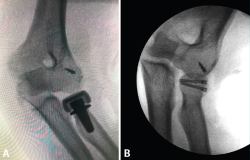

Figura 10. Evaluación intraoperatoria de la lesión del ligamento colateral medial (LCM) mediante la maniobra de varo forzado. A: inestabilidad persistente con luxación ulnohumeral a pesar de la reparación del complejo del ligamento colateral lateral (LCL); B: codo estable tras la reparación del LCL con la maniobra de varo forzado.

Figura 11. Radiografías de control en proyección anteroposterior y lateral en un paciente afecto de inestabilidad simple de codo persistente en el que se le realizó una reparación aguda del ligamento colateral lateral (LCL) y del ligamento colateral medial (LCM) mediante un sistema de arpones y suturas.

Típicamente, suele realizarse la reducción abierta mediante un abordaje posterior de codo o un abordaje lateral y medial combinado. En primer lugar, se aborda la zona lateral de la articulación del codo mediante un abordaje lateral de Kocher para realizar una inspección en busca de fragmentos óseos condrales o partes blandas interpuestas. El siguiente paso sería la reparación de LCL, el cual suele estar avulsionado de su inserción más proximal en el epicóndilo. La reparación típicamente se realiza mediante un sistema de anclaje con suturas, siendo importante también la posible lesión muscular de la región extensosupinadora. Una vez realizada la sutura de la zona ligamentosa y muscular lateral, se realiza una exploración bajo control escópico para evaluar la estabilidad del codo en rangos medios de movilidad y en posición de rotación neutra y pronación (evaluar la estabilidad del codo en supinación puede poner en riesgo la reparación del LCL). Si el codo sigue siendo inestable, entonces debe tenerse en cuenta realizar una reparación del LCM (Figura 10). Al igual que sucede con el LCL, la lesión del LCM suele localizarse en su inserción más proximal, aunque en ocasiones puede estar avulsionado del tubérculo sublime. La técnica de reparación empleada también suele ser mediante un sistema de arpón con suturas y, tras la realización de esta, deben repararse las lesiones asociadas en la musculatura flexopronadora (Figura 11). Si tras la reparación del LCL y del LCM, el codo sigue siendo inestable, debe colocarse un fijador externo de codo durante unas 4-6 semanas. Puede usarse, en función de las preferencias del cirujano, un fijador externo fijo o articulado.